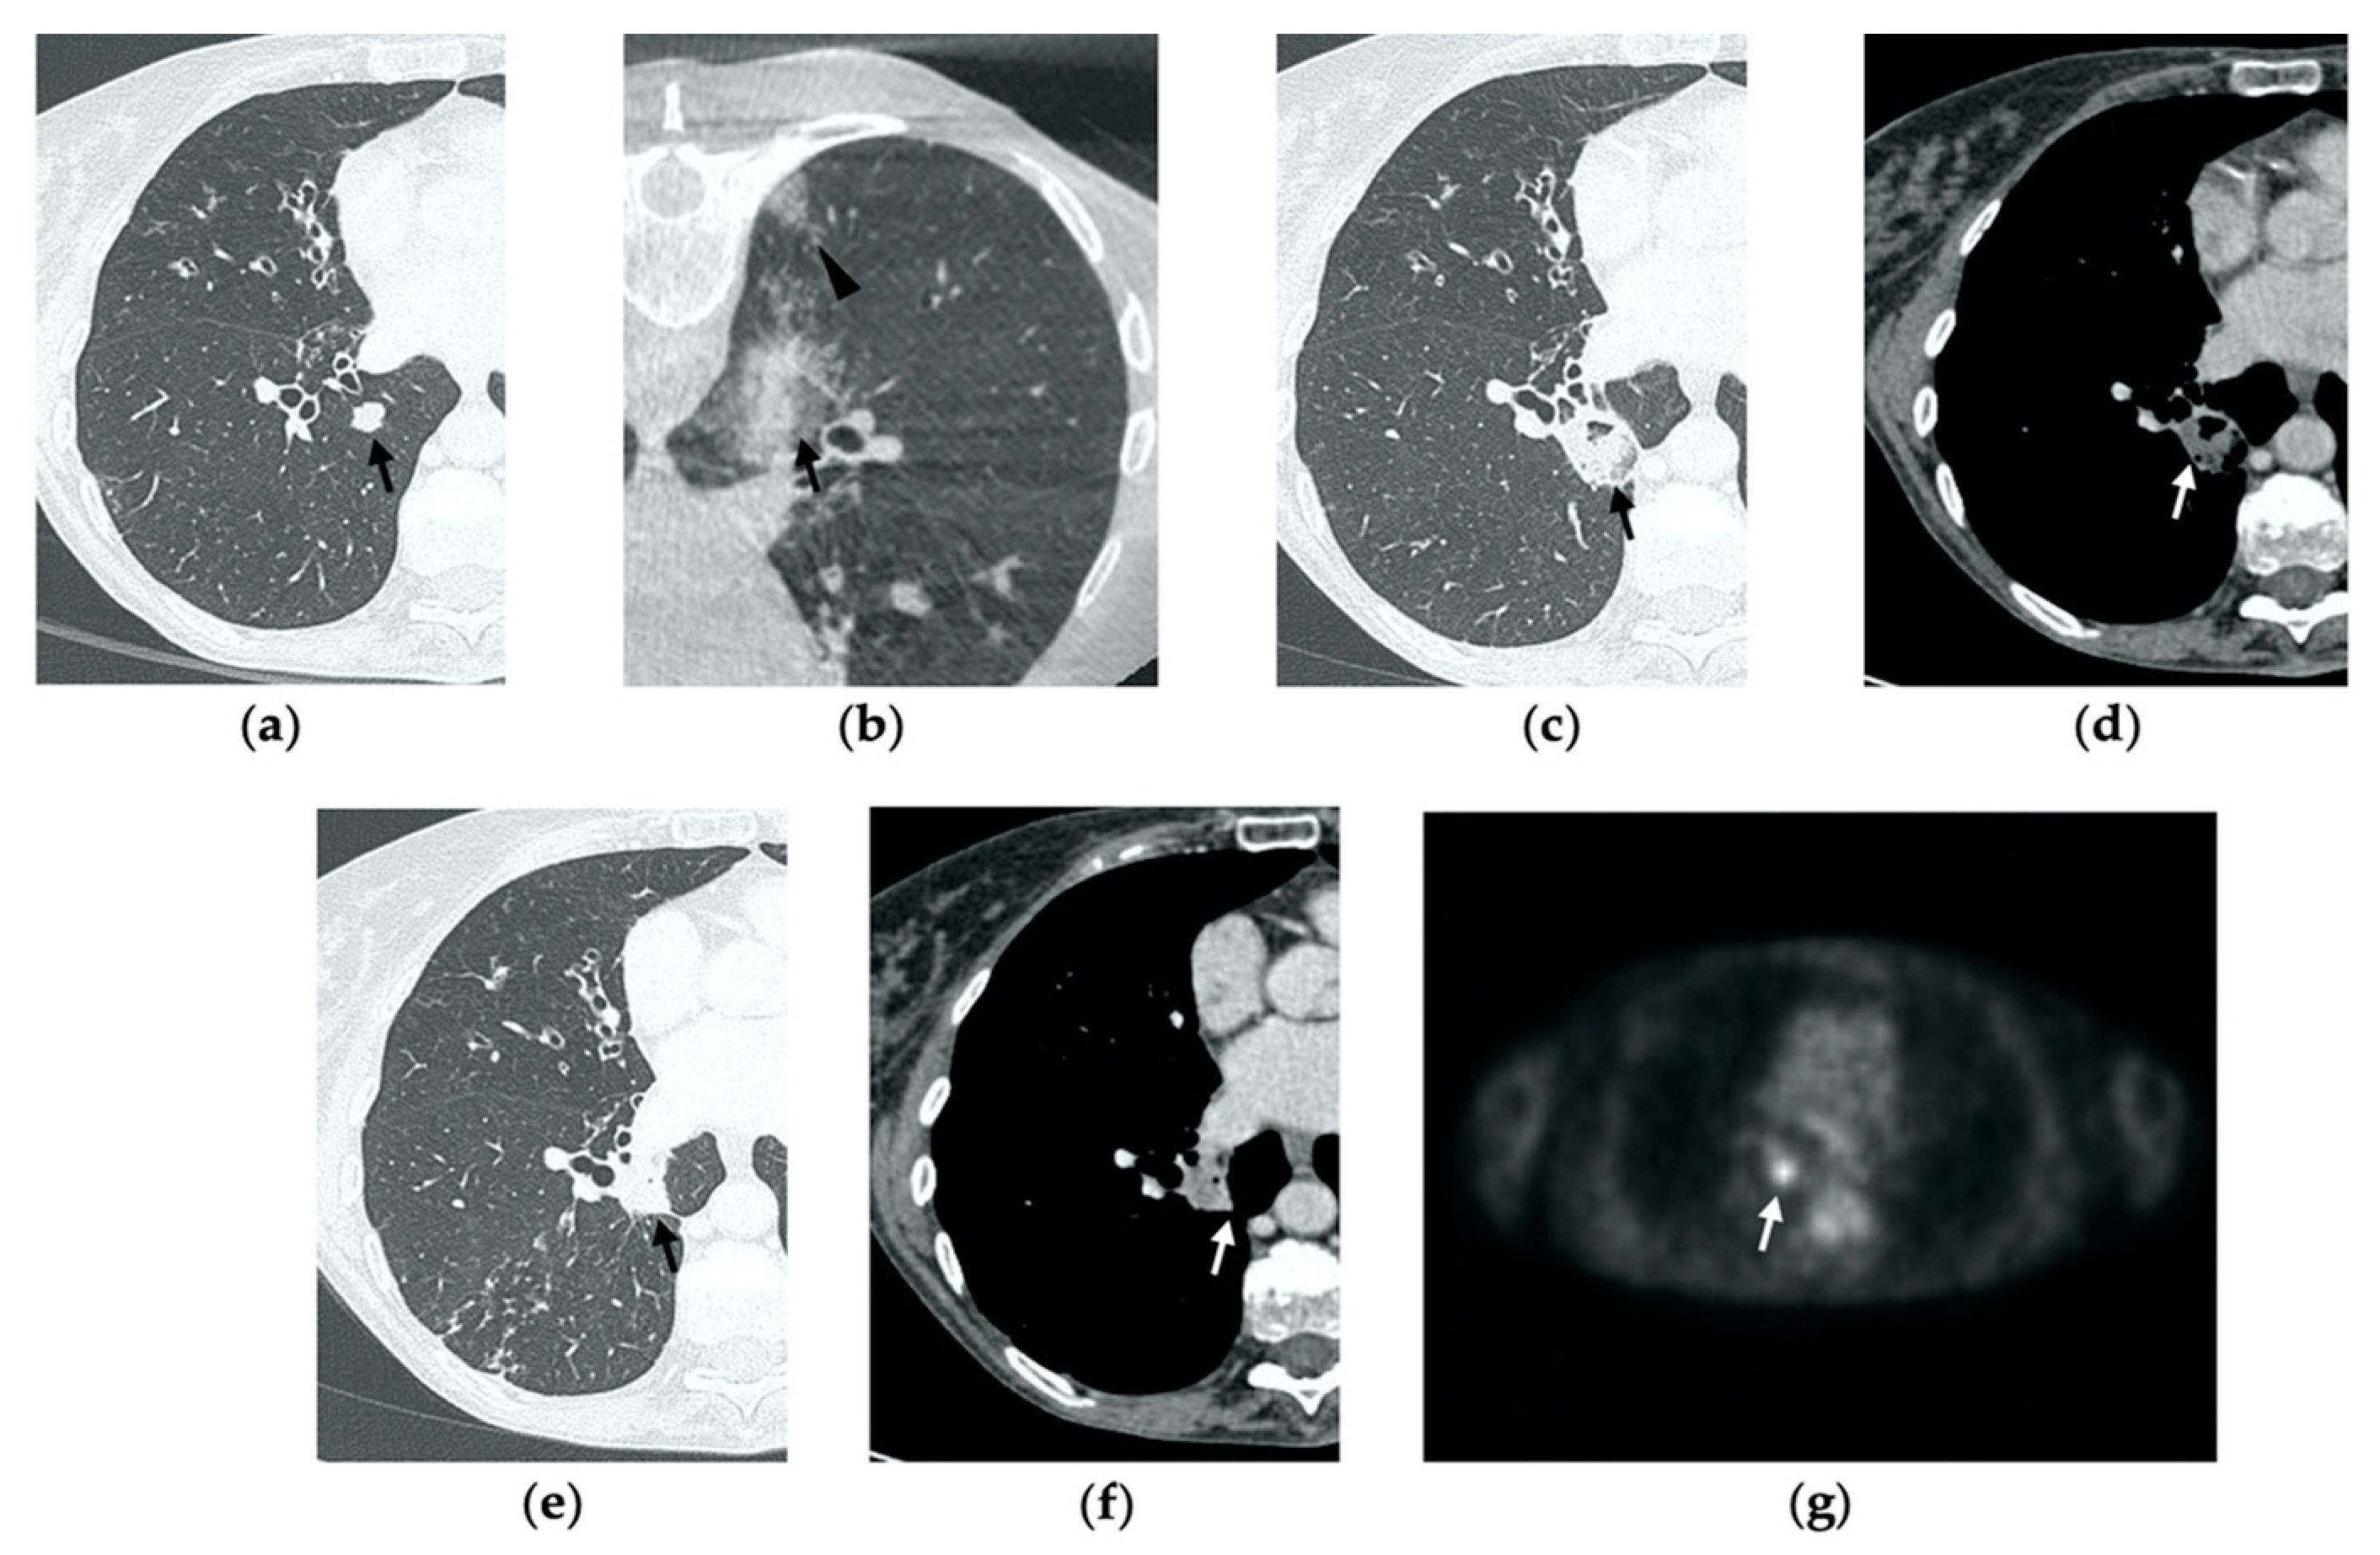

Figure 4. 63-year-old-woman (same patient in Figure 3) with pulmonary metastasis from CRC in the right upper lobe. (a) Axial CT before treatment (black arrow). (b) Cone-beam CT image obtained at the end of the procedure shows GGO (black arrow) around the treated lesion. (c,d) Axial 2-month follow-up CT images show an elongated consolidation with hypoattenuating bubbles (black arrow) and no contrast uptake (white arrow). (e,f) Axial 5-month follow-up CT images demonstrate a tiny nodular uptake of contrast on the posterior margin of the consolidation (white arrow), suggestive of residual disease. (g,h) On axial CT images after 8 months the nodular enhancement persists (white arrow). (i) PET/CT image at 9 months proves residual disease on the treated lesion (white arrow) as well as simultaneous metastasis (white arrowhead) in the posterior segment.

At all stages of follow-up, the appearance of either central or peripheral nodular or irregular enhancement should be considered as residual or recurrent disease (Figure 4f and Figure 5f), since the ablated area undergoes fibrous transformation, and it should not show contrast enhancement, except for the persisting peripheral safe zone [7,15].

On CT images obtained at 3-month follow-up, the size of the ablation zone should be the same or still larger than the baseline tumor, although it undergoes further involution compared to the early phase, as during the fibrosis process the wall thickness and the previously depicted cavities progressively decrease (Figure 1d) [7]. The attenuation of the ablated tissue decreases, as there is no more central contrast material uptake in relation to the local necrotic changes, while the peripheral benign enhancement may persist or decrease (Figure 1e). Overall, the size of the ablation area at this stage should become stable along with a decrease in wall thickness [7,8].

After 6 months, the ablation site undergoes further involution and there should not be any inner contrast enhancement, except for the persistent benign periablational area (Figure 2f,g) [7]. The previously mentioned cavities decrease in size and may completely disappear. CT images may show fibrotic scarring without contrast enhancement and mild architectural parenchymal distortion of the surrounding lung (Figure 1f,g) [24]. At this stage, small treated nodules may already show a linear fibrotic evolution on CT images (Figure 2h,i).